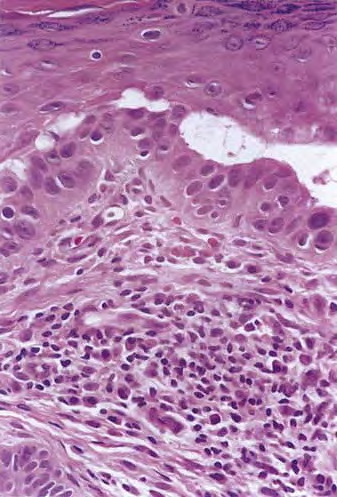

Acantholytic actinic keratosis =انحلال الاشواك في التقران الضيائي